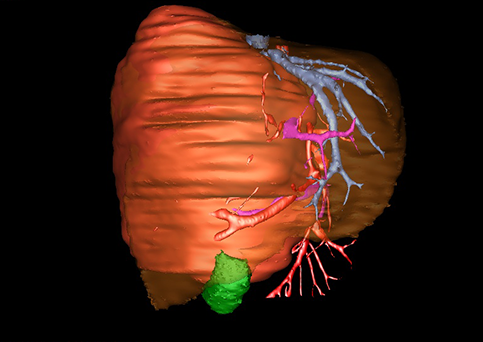

近年来由于数字医学的发展,基于可视化三维重建技术的计算机辅助手术系统极大推进了小儿肝脏肿瘤的精准手术的进步。可以立体透视肝脏解剖、精确掌握肝段的边界、精确测算肝段乃至任意血管所支配的功能体积、准确定位病灶及其与邻近血管的解剖关系,最终对不同手术方案进行比较、筛选和优化。因此,计算机辅助手术规划系统是实现精准肝切除的有力辅助工具,是未来数字外科、精准外科等21世纪外科新理念的重要技术支撑。

计算机辅助手术规划系统具有良好的操作可行性、计算准确性和三维显示效果,可半透明、交互式显示真实的肝内立体解剖关系和空间管道变异,准确计算肝内管道的直径、走行角度,两点间的垂直距离,和任意血管的支配或引流范围等传统二维影像无法获取的信息,有助于实施个体化手术,提高了手术的确定性、预见性和可控性。计算机辅助手术规划系统可直观显示预留肝脏的结构和功能,并可通过虚拟切割功能辅助术者对手术方案进行蹄选和优化,系统评估手术风险和制定对策,改变了部分二维规划的术式和切除范围,使部分二维规划认为不能切除的患者成功手术,提高了手术的根治性、安全性和病变的可切除性,更加符合精准肝脏外科的术前规划要求。详见第11章。

随着计算机技术及影像检查技术的不断发展,以精确的术前影像学和功能评估、精细的手术操作为核心的精准肝切除技术日益受到重视。基于数字医学的计算机辅助手术技术(computer-assisted surgery,CAS)则是实现肝脏精准手术操作的基础。计算机辅助手术系统(CAS)可将术前二维(two dimensional,2D)的CT/MRI影像数据进行三维(three dimensional,3D)重建,建立个体化的肝脏三维解剖模型,清晰显示肝脏内脉管系统的走行及解剖关系,还原病灶与其周围脉管结构的立体解剖构象,准确地对病变进行定位、定性和评估,制定合理、定量的手术方案,实施个体化的肝脏血管取舍分配方案及实施精准肝脏手术。一般认为CAS包括:创建虚拟的患者的图像;患者图像的分析与深度处理;诊断、手术前规划、手术步骤的模拟;术中实时导航。应用本技术后,由于可以更清晰地看出肿瘤的界限,特别是根据肝血管的显影,判断出肿瘤与门静脉及肝静脉的关系以在手术前较准确地估计出手术成功切除的可行性。以往部分根据普通强化CT判断无法手术的病例而被评估为可以成功切除并手术成功。